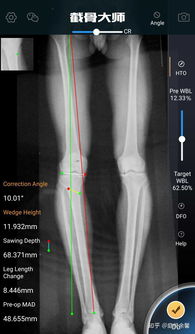

骨癌医学示意图

医生为病人检查骨科X光片